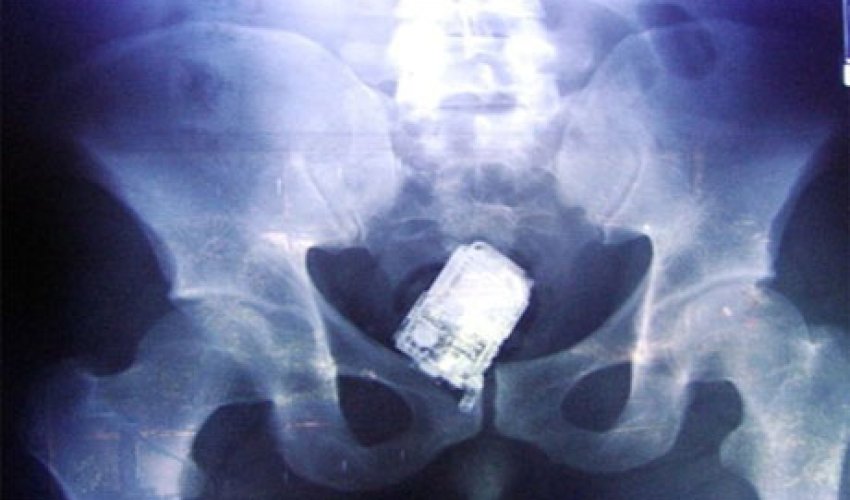

İnsan nələri udmağa qadir deyil? Yaxud mədədən nələr gəlib-keçmir? ANN.Az-in oxuculara təqdim etdiyi fotolar bir daha insanın nələrə qadir olduğunu göstərir. 1. İlan balığı2. Qaşıq3. Batareyalar4. Canlı qurbağa5. Mismar6. Dərmanlar 7. Nişan üzüyü8. Qayçı9. Tük yumağı10. Mobil telefom11. Qələm12. Yay13. Əl bombası14. Açar15. Lampa